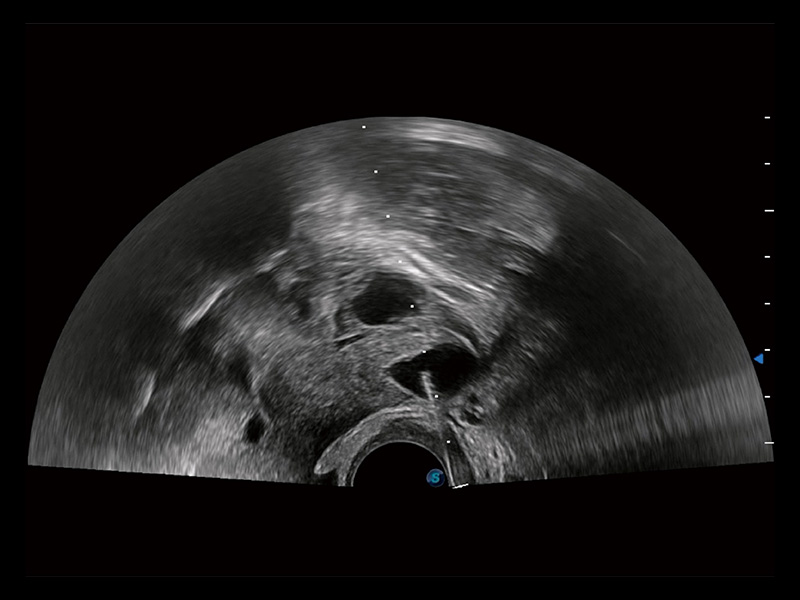

单角子宫